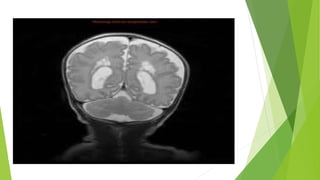

MRI Brain

 the literature suggests that MRI should be strongly considered in all cases; in

one study, 89% children with cerebral palsy were found to have abnormal

MRIs. [37] Additionally, MRI may have a role in predicting neurodevelopmental

outcomes in preterm infants. [38] See the following images.

Normal MRI Brain

 Normal results from neuroimaging studies do not exclude a clinical diagnosis

of this disorder. However, in these cases, other underlying metabolic and

genetic etiologies should be considered and excluded before diagnosing a

child with cerebral palsy.